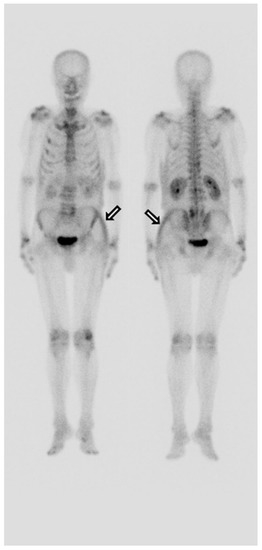

Despite conservative management, he complained of severe pain in the left hip. On the fifth day of admission, a whole-body bone scan was performed to determine if there was any other fracture. A technetium-99m methylene diphosphonate (MDP) whole-body bone scan showed an increased uptake noted in the left buttock and left flank and no other site of fracture (Figure 3). The area where the radioactivity was increased matched the location and shape of the lesion where the signal change was seen on the MRI. Furthermore, upon physical examination, we can see a considerable ecchymosis involving the left lateral chest region extending to the left buttock (Figure 4). Mild tracer uptake was also noted in the left facet joint of L4/L5, which is consistent with significant degenerative arthrosis seen on recent lumbar CT images. The osteoid formation and dystrophic calcification are thought to be the mechanisms that mediated a significant number of radiopharmaceuticals in the hematoma on whole-body bone scans [1]. The pathogenesis of the uptake of bone scanning agents in soft tissue is multi-factorial. One of the primary underlying factors is excess calcium in the soft tissue. Mechanisms leading to increased extraosseous 99mTc-MDP uptake include excess calcium in the soft tissue, extracellular fluid expansion, enhanced regional vascularity and permeability, and elevated tissue calcium concentration [2]. In this case report, 99mTc-MDP uptake in gluteal hematoma is thought to be due to excess calcium and enhanced permeability in the soft tissue. Although there is no visible calcification, the accumulation of bone tracer is possible even by microcalcification. Finally, a hematoma was confirmed based on several imaging modalities. Our patient was managed conservatively with analgesic and stopping anticoagulants. The hematoma in the soft tissue of the gluteal region is a rare occurrence and is usually seen in patients taking an oral anticoagulant, having obesity, and facing falls. Contrasted with MRI or CT findings, we could not find any fracture on the bone scan. This false-negative finding for fracture is considered attributable to the fact that for older adults, the result of bone scans may appear normal even ten days after the fracture [3]. It is well established that SPECT (single-photon emission computed tomography) or SPECT/CT (SPECT/computed tomography) has better accuracy than planar scintigraphy. SPECT/CT especially reduces the rate of equivocal lesions compared to planar bone scan due to better anatomic localization of lesions and higher lesion-to-background contrast, with increased diagnostic accuracy over SPECT alone or planar scintigraphy alone [4]. These can contribute to identifying early fractures. If SPECT or SPECT/CT had been performed on this patient, early fracture findings showing only a very slight increase in tracer uptake might have been discovered. Unfortunately, we did not have the equipment in our institution, so SPECT/CT could not be performed on the patient.

Figure 4. On physical examination, the left flank and left hip showing ecchymosis.